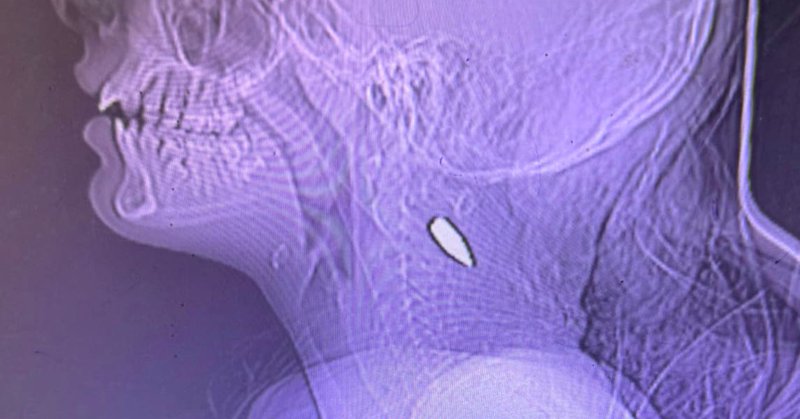

Eines der evakuierten palästinensischen Kinder in der Schweiz hat eine Scharfschützen-Schusswunde. Das ist offenbar kein Einzelfall.